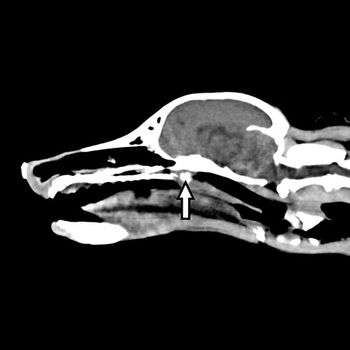

Brachy breeds are as popular as ever with pet owners, and as a result, veterinarians continue to see patients with respiratory aberrations associated with BOAS. A board-certified surgeon offers the latest options to treat these conditions in dogs.

When a veterinary patient presents with sneezing and obstructive nasal breathing in your practice, how are you diagnosing the patient? Take the quiz to see if you're right.